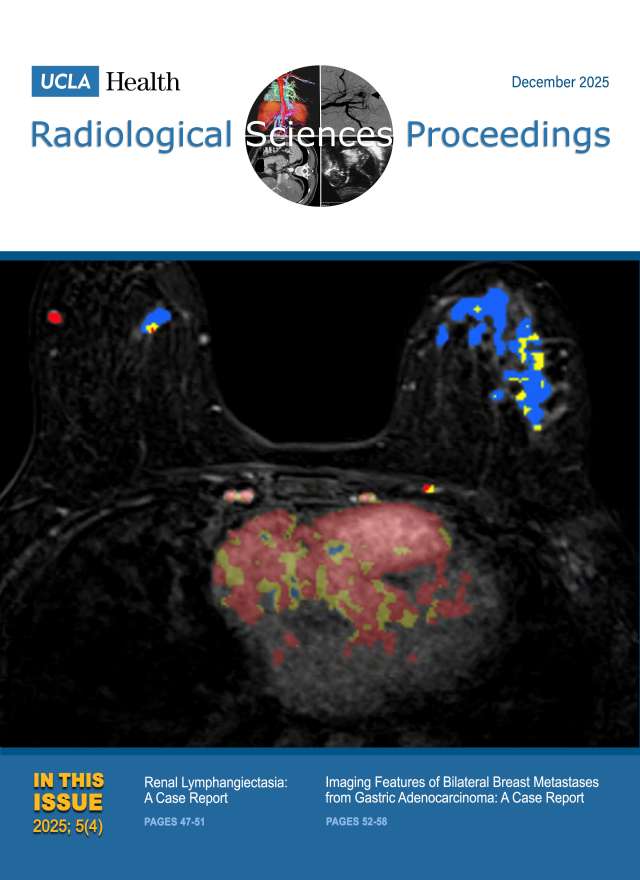

December 2024

Volume 4, Issue 4

- Smoking-Related Interstitial Lung Disease: CT Image-Based Review and Update

- Postcholecystectomy Syndrome due to Prominent Remnant of the Cystic Duct and Choledocholithiasis: A Case Report

- Kommerell Diverticulum and Agenesis of the Left Common Carotid Artery in a Patient with Dysphagia: A Case Report

- Extensive Subcutaneous Calcinosis and Hypercalcemia in the Setting of Mineral Oil-Injection-Related Foreign Body Reaction: A Case Report